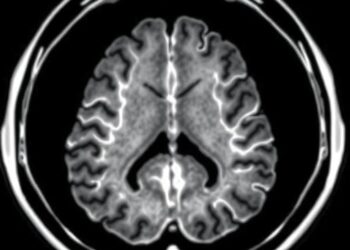

18F-FAPI PET/CT Reveals Lung Cancer Brain Metastasis Rates

A groundbreaking study published in BMC Cancer introduces novel insights into the detection of brain metastases (BM) originating from various ...